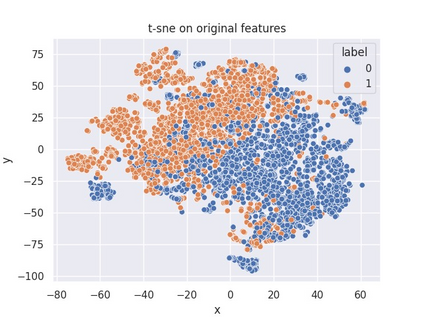

Multiple instance learning (MIL) is a powerful approach to classify whole slide images (WSIs) for diagnostic pathology. A fundamental challenge of MIL on WSI classification is to discover the \textit{critical instances} that trigger the bag label. However, previous methods are primarily designed under the independent and identical distribution hypothesis (\textit{i.i.d}), ignoring either the correlations between instances or heterogeneity of tumours. In this paper, we propose a novel multiplex-detection-based multiple instance learning (MDMIL) to tackle the issues above. Specifically, MDMIL is constructed by the internal query generation module (IQGM) and the multiplex detection module (MDM) and assisted by the memory-based contrastive loss during training. Firstly, IQGM gives the probability of instances and generates the internal query (IQ) for the subsequent MDM by aggregating highly reliable features after the distribution analysis. Secondly, the multiplex-detection cross-attention (MDCA) and multi-head self-attention (MHSA) in MDM cooperate to generate the final representations for the WSI. In this process, the IQ and trainable variational query (VQ) successfully build up the connections between instances and significantly improve the model's robustness toward heterogeneous tumours. At last, to further enforce constraints in the feature space and stabilize the training process, we adopt a memory-based contrastive loss, which is practicable for WSI classification even with a single sample as input in each iteration. We conduct experiments on three computational pathology datasets, e.g., CAMELYON16, TCGA-NSCLC, and TCGA-RCC datasets. The superior accuracy and AUC demonstrate the superiority of our proposed MDMIL over other state-of-the-art methods.